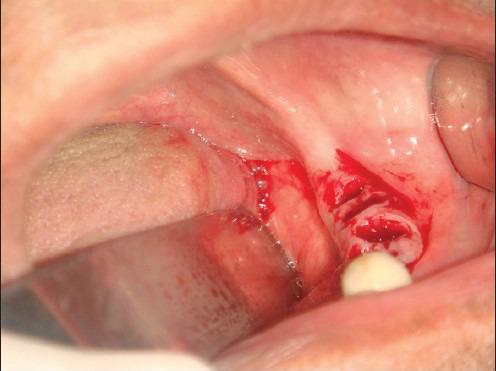

The replacement of missing teeth with implant-borne restorations has become a treatment modality accepted by the scientific community for fully and partially edentulous patients. Recent reports have demonstrated the successful placement of dental implants into the fresh extraction socket in the anterior as well as in molar regions, which is made possible due to modification in implant surface. The present case report highlights the placement of three bicortical screw (BCS) implants into the fresh extraction sockets and one KOS implant in edentulous area with flapless technique. All the implants were immediately loaded and followed up for a period of 6 months.

用种植体支持的修复体替代缺失牙已成为科学界认可的针对全口和部分牙列缺失患者的一种治疗方式。近期报告显示,由于种植体表面的改良,已成功将牙种植体植入前牙区以及磨牙区的新鲜拔牙窝。本病例报告重点介绍了采用不翻瓣技术将3枚双皮质骨螺钉(BCS)种植体植入新鲜拔牙窝以及在无牙区植入1枚KOS种植体的情况。所有种植体均即刻负重,并随访6个月。